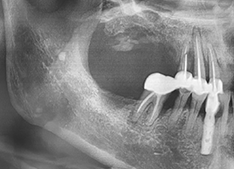

서울탑플란트 치료사례

어떠한 임플란트 케이스도 문제없이 치료가 가능합니다

A2. 임플란트 시술은 CT 촬영으로 잇몸뼈 상태를 확인한 뒤,

인공치근을 식립하고 치유 기간을 거쳐 보철물을 장착하는 과정으로 진행됩니다.